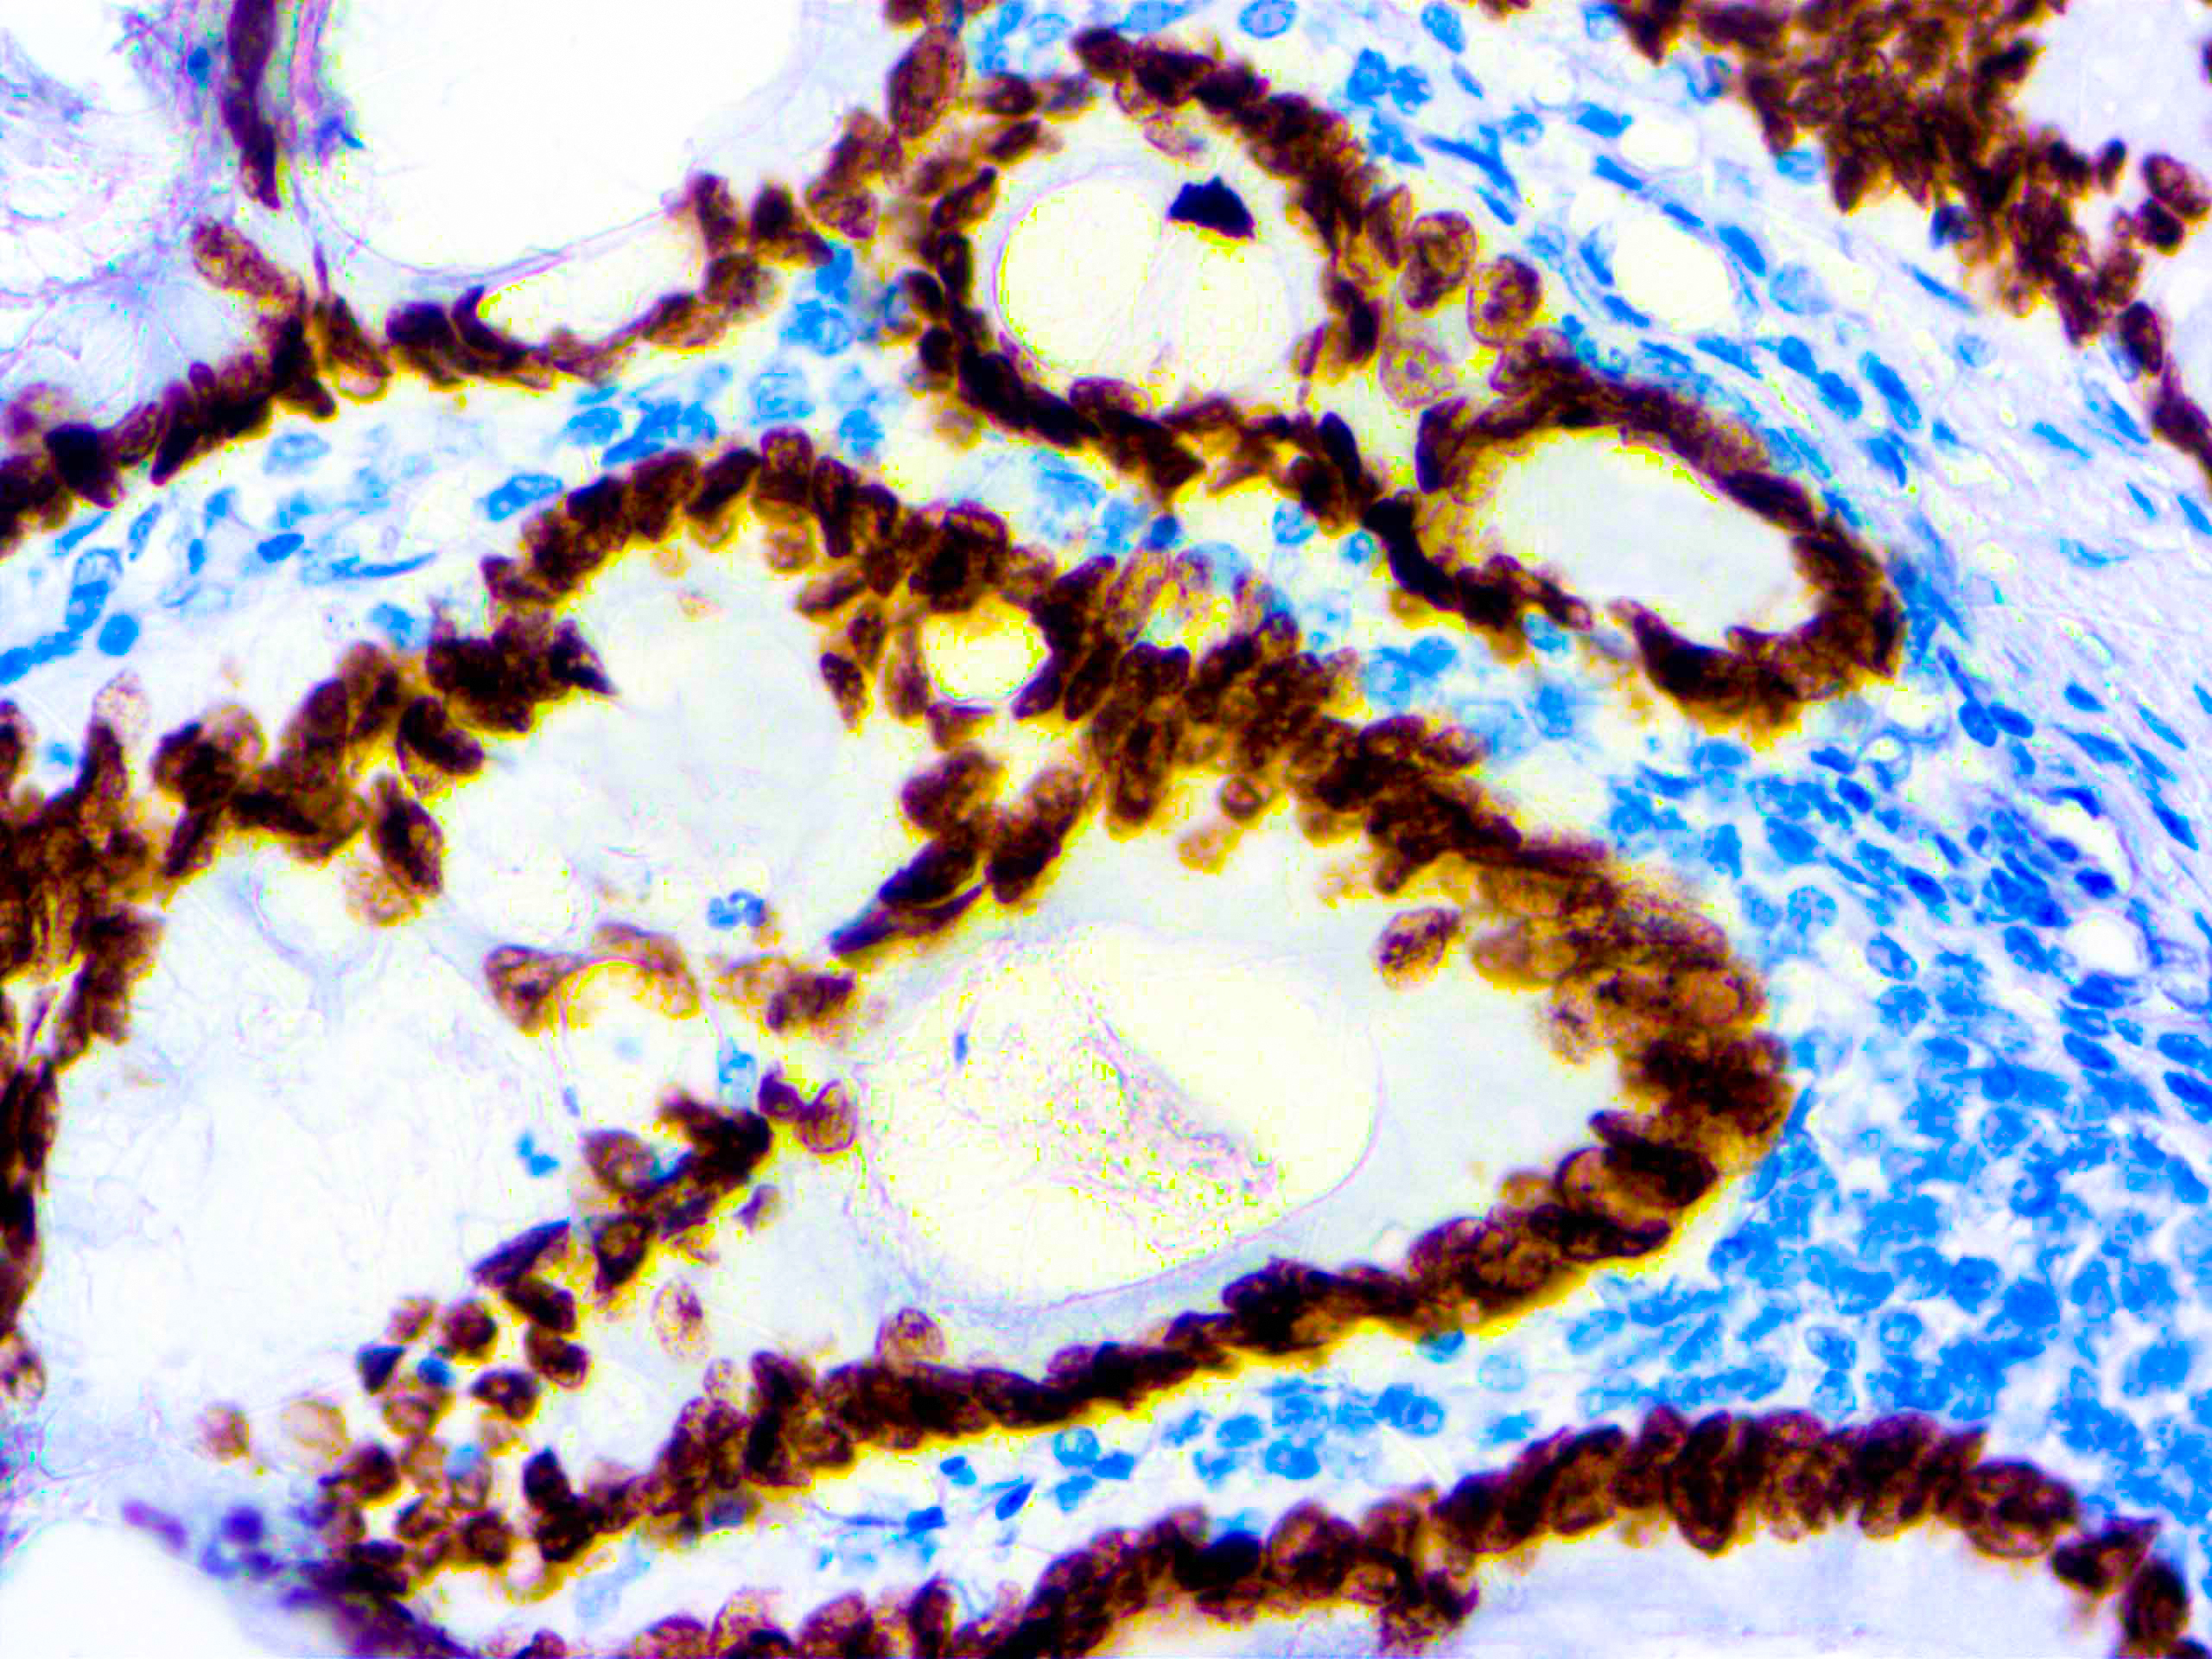

formalin fixed paraffin embedded human Colon Ca stained with SATB2 40x Published December 6, 2021 at 2560 × 1920 in formalin fixed paraffin embedded human Colon Ca stained with SATB2 40x formalin fixed paraffin embedded human Colon Ca stained with SATB2 40x formalin fixed paraffin embedded human Colon Ca stained with SATB2 40x ← Previous Next →